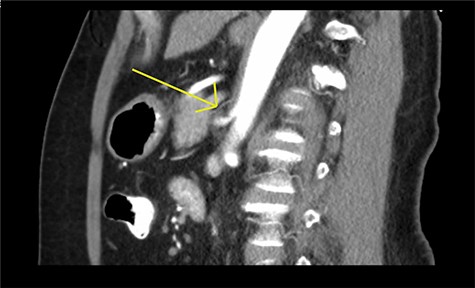

A 61-year-old female presented with a 1 year history of intermittent epigastric pain worsened by eating, nausea and diarrhea. She had a past medical history of hypertension, irritable bowel syndrome and GERD. CT imaging revealed celiac artery stenosis and a possible MAL syndrome (Fig. 1). No other causes were identified (normal EGD, normal barium swallow and no improvement with non-pharmacological measures). The case was extensively discussed and there was a consensus to proceed to surgery.